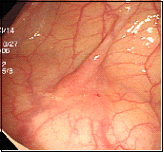

通常の観察では、わずかに発赤しているのみです。

NBIという特殊光モードにすることで、コントラストがはっきりします。